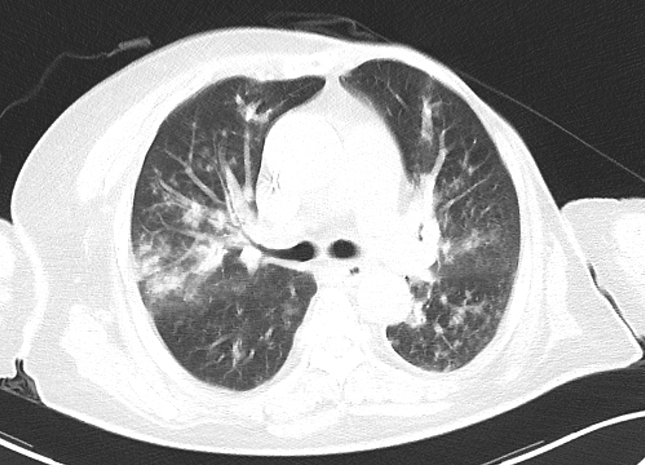

随即复查胸部CT发现

两肺炎症与之前CT相比明显进展

▲患者胸部CT:两肺感染,支气管壁增厚、管腔狭窄